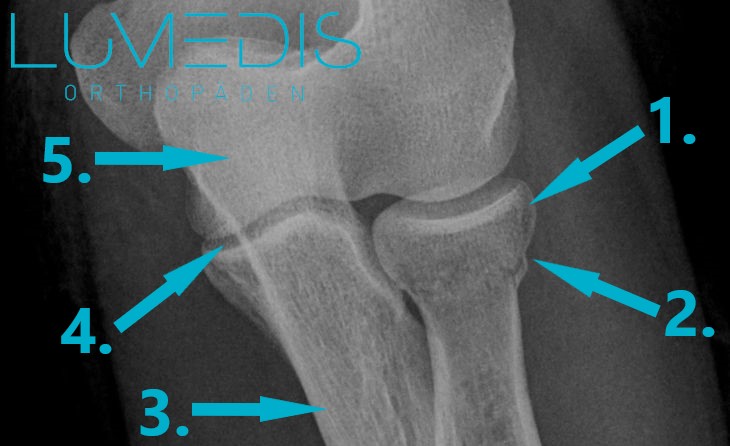

Röntgenbild einer Radiusköpfchenbruchs von der Seite

Röntgenbild einer Radiusköpfchenfraktur Mason Typ II

Die Anfertigung eines Röntgenbilds ist bei einem Verdacht auf eine Radiusköpfchenfraktur fast immer notwendig.

Durch das Röntgenbild kann eine näheren Bestimmung des Bruchs (Enteilung nach Mason) durchgeführt werden.

Im Röntgenbild können die Knochen gut dargestellt werden, weshalb es sich als schnell-durchführbare Methode sehr gut eignet.

Röntgenbild eines Ellenbogens mit einer Radiusköpfchenfraktur (a.p.) (Zielaufnahme Radiusköpfchen)